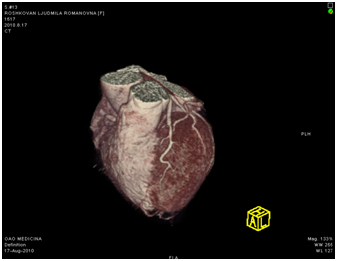

МСКТ коронарных артерий от 08.2010

Ствол ЛКА широкий, имеет ровные контуры, не стенозирован. ПНА в проксимальном сегмента имеет неровные контуры за счет кальцинированных и частично кальцинированных бляшек, просвет артерии на этом уровне сужен до 30-50%, в среднем сегменте определяется ряд пристеночных и циркулярных мягких бляшек, со стенозом артерии до 60-75%, дистальные отделы артерии малого калибра, плохо заполняются контрастным веществом. ОА нормального диаметра, заполняется контрастным веществом без признаков гемодинамически значимого стеноза. ПКА нормального диаметра, в проксимальном сегменте имеются смешанные частично кальцинированные бляшки, стенозирующие просвет до 30%, в среднем сегменте визуализируется пристеночная смешанная бляшка, стенозирующая просвет до 50-70%, дистальный сегмент не изменен. Правый тип коронарного кровоснабжения.

18.08.2011 выполнена селективная коронарная ангиография.

Огибающая коронарная артерия без признаков стенозирующего атеросклероза.

Правая коронарная артерия – в средней трети стеноз 70%. Правый тип коронарного кровообращения.

Передняя межжелудочковая артерия

Правая коронарная артерия

18.08.2011 интервенционным кардиохирургом в область стеноза проксимальной трети передней межжелудочковой артерии проведен баллонный катетер со стентом «Мульти-линк 8» размерами 3×12 мм, произведена имплантация.

В дистальную часть правой коронарной артерии проведен проводник 0,014″. В область стеноза проведен баллонный катетер со стентом «Мульти-линк 8» размерами 3×12 мм, произведена имплантация.

На контрольных ангиограммах получен хороший кровоток